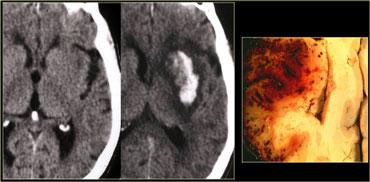

Nhồi máu xuất huyết

15% nhồi máu MCA ban đầu có tính chất xuất huyết.

Xuất huyết được phát hiện dễ dàng nhất trên CT, nhưng cũng có thể được hiển thị bằng chuỗi xung MRI gradient echo.